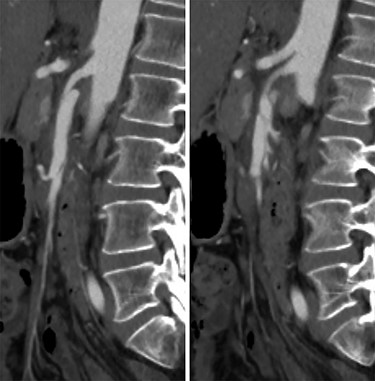

She was admitted and maintained on bowel rest and heparin infusion. Given persistent pain after 2 days of non-operative management, an abdominal arteriogram was performed through a left axillary artery cutdown. The dissection was identified 1.5 cm distal to the origin of the SMA (Fig. 2). Intravascular ultrasound was used to determine diameters and landing zones for stent placement (Fig. 3). The dissection was initially treated with a 6 mm × 40 mm self-expanding stent followed by post-dilation with 4 mm × 40 mm and 6 mm × 40 mm balloons. A 5 mm × 19 mm stent graft was deployed proximally with small overlap and ~3-mm extension into the aorta. Completion angiogram showed <10% residual stenosis (Fig. 4). As the right external iliac artery dissection was small and asymptomatic, no intervention was performed.

Pre-stenting angiogram of the SMA demonstrating early filling of the false lumen including the middle colic artery.